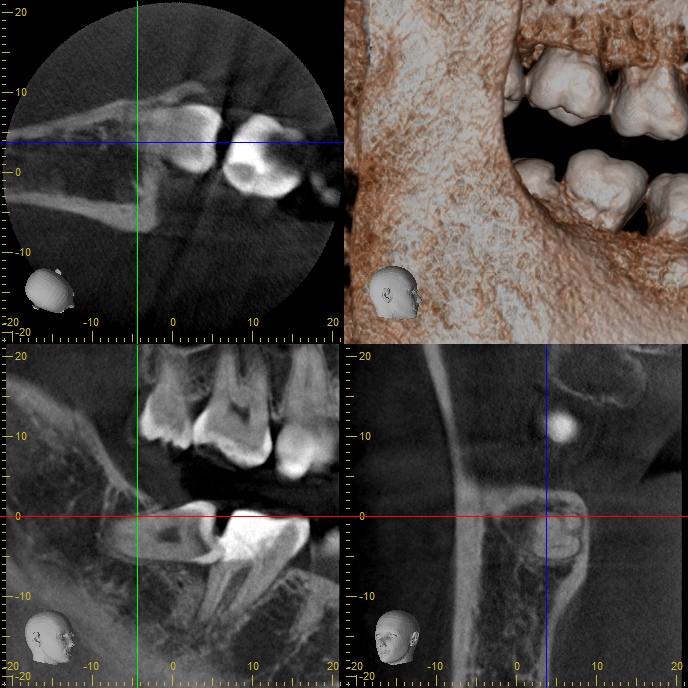

右下奥歯が腫れた 30代男性 親知らずの抜歯

親知らずの周囲の炎症

頭の部分が手前の歯にぶつかっていたので、その部分をカットしてスペースを作ったのち、抜歯をしています。

黒くなっている部分が虫歯で、白くなっているのがプラークと呼ばれる細菌の塊です。歯茎の中にあったので歯ブラシ等では届かないためこのようになったと思われます。